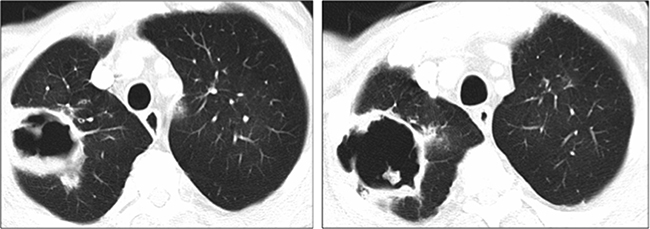

A 62-year-old man was incidentally diagnosed of a hepatocellular carcinoma in the advanced stage due to branch portal vein invasion, as well as alcohol-related cirrhosis (Child Pugh A5). His medical history included a diagnosis of severe chronic obstruction pulmonary disease (COPD), arterial hypertension and peripheral arteriopathy. As part of a lung cancer screening program, he had a chest CT-scan performed a year before receiving Sorafenib which showed mild paraseptal emphysema in upper and lower lobes with no bullae. Selective TARE was followed by an objective prolonged tumor response. One year after TARE, a total body CT showed no signs of extrahepatic disease. Five months later, he reported abdominal pain and a liver MRI revealed liver progression. Sorafenib was started at 800 mg daily but later reduced to 400 mg daily due to intense asthenia and weight loss. The patient had usually two COPD exacerbations per year. Exacerbations were more frequent after the start of Sorafenib and he required antibiotics and systemic corticosteroids. One year after Sorafenib was initiated, he developed cough and progressive dyspnea and a chest CT scan showed a pneumatocele (Figure 3). Sorafenib was discontinued and amoxicillin-clavulanic acid was prescribed with symptom relief. Weeks later, an Aspergillus fumigatus was isolated in a sputum culture and oral voriconazol was introduced despite the good response to antibiotics. A new CT one month after discontinuation of Sorafenib showed a slight reduction in the size of the pneumatocele. Sorafenib was reintroduced at the same reduced dose.

Figure 3: Lung cavity at diagnosis in the right upper lobe (120 × 60 × 60 mm) (Case 2).

Three months after restarting Sorafenib treatment, he again had asthenia, cough and purulent sputum. A chest X-ray showed an enlarged pneumatocele (Figure 4). Empiric antibiotic therapy with clindamicyn and voriconazol was prescribed. Aspergillus fumigatus was again isolated in the sputum but not in the BAL culture. Symptoms improved although the size of the cavity remained stable. Sorafenib was permanently discontinued after 14 months, recessed and the patient died one month later because of tumor progression.